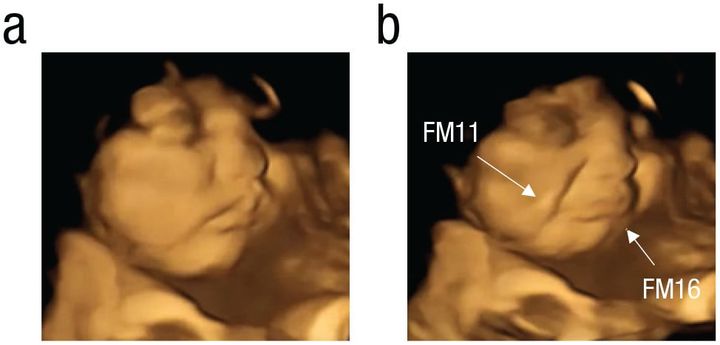

こちらはケール味を感じた胎児の表情ですが、上のニンジン味のときと違って、明らかに口元が歪んでいるのが見て取れますね。

ケール味にさらされた後、胎児は「泣き顔」になった/Credit: Beyza Ustun et al., Psychological Science(2022)